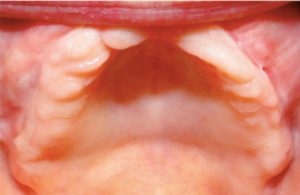

Case 1

Gus is a 60-year-old man who has been gradually been losing his teeth over the past 20 years and wanted to replace the missing teeth and save what he had left. Unfortunately, he presented with advanced periodontal (gum) disease and all his remaining upper teeth had to be removed. He decided to proceed with 17 dental implants so he could enjoy a FIXED crown and bridge and never have to remove his teeth.

Before